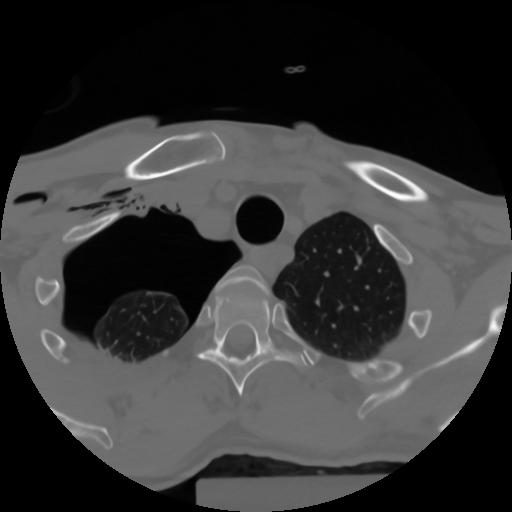

10 P.BLANDAS,,Axial,2.0,P.BLANDAS,,